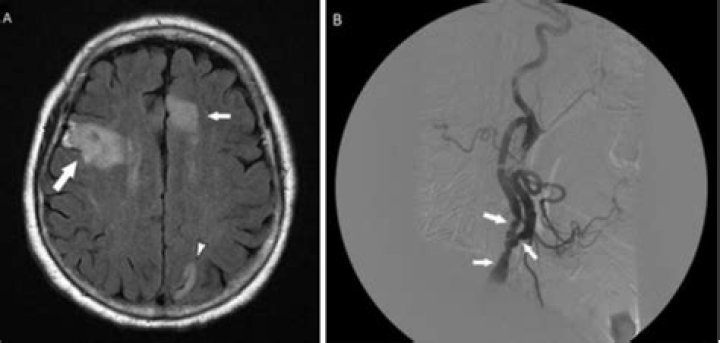

Can brain MRI show vasculitis?

In order to detect a cerebral vasculitis, MRI studies, including diffusion, gradient echo and contrast enhanced T1 sequences, are necessary [9,17,18]. Frequently, both new and older ischaemic lesions are detected; the combination of ischaemic and haemorrhagic lesions is not uncommon.

Does MRI show vasculitis?

MRI / MRA: MRI is another imaging modality that can be useful for diagnosing and following systemic vasculitis; particularly large vessel vasculitis. MRI allows for visualization of the vessel wall. In vasculitis, the vessel wall may be thickened or edematous.